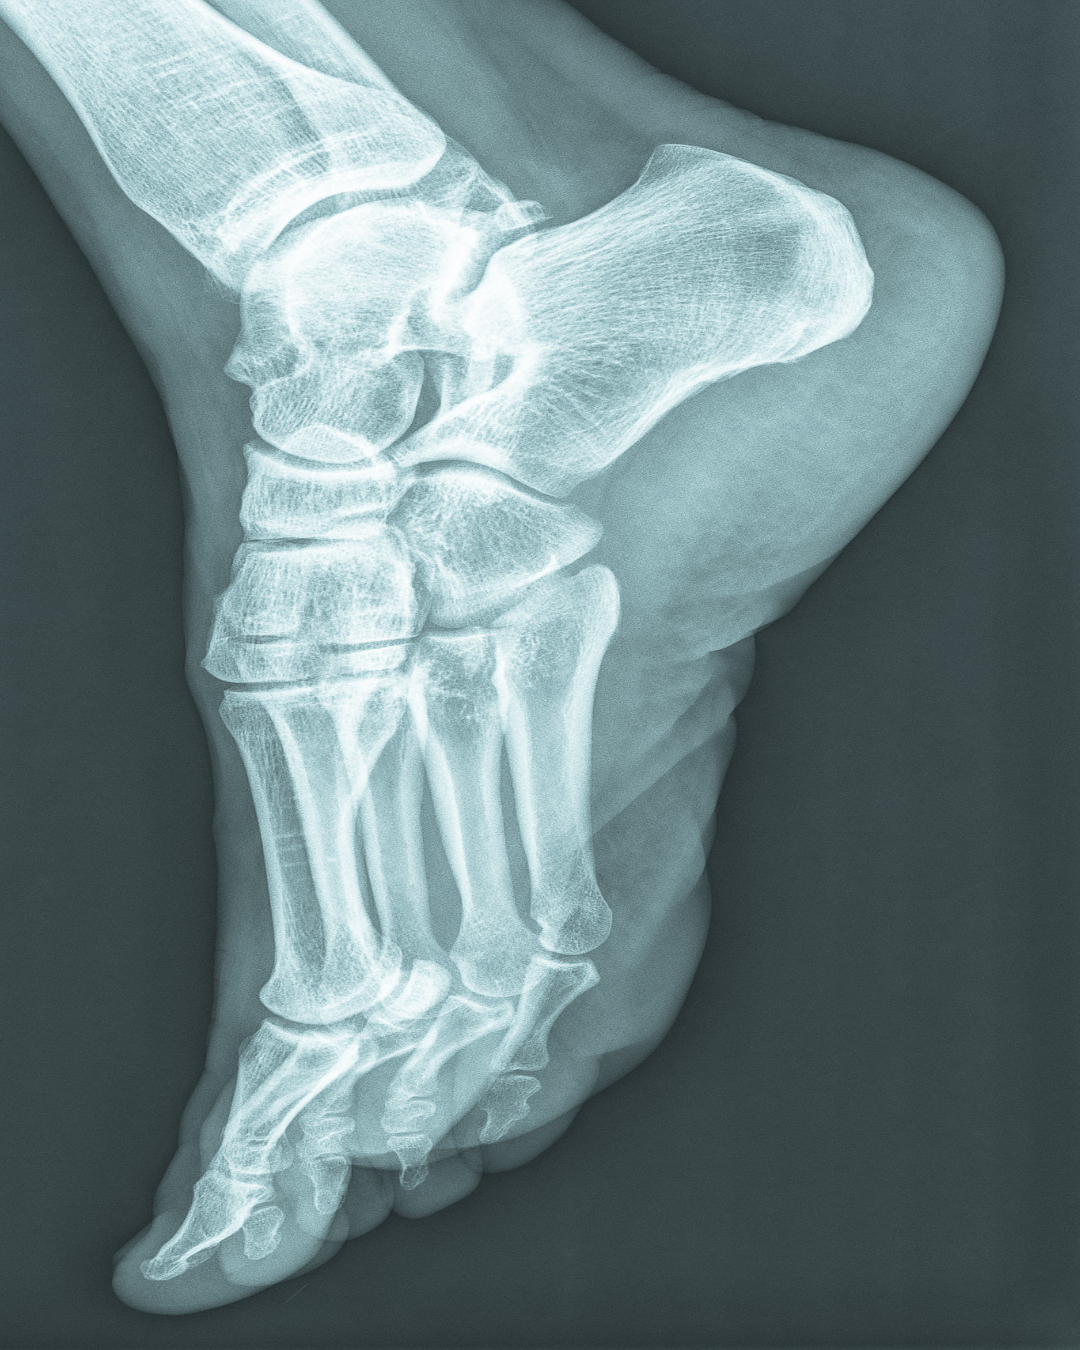

It is important to differentiate the condition of the fascia. Often, an inflammation (fasciitis) is confused with a deteriorated quality of the fascia. (tendinopathy). The difference can be made visible with an ultrasound scan.

If the stretch of the fascia is prolonged, an extra piece of bone will develop at the insertion of the heel: the heel spur. This is the end stage of a long process and not easy to fix.